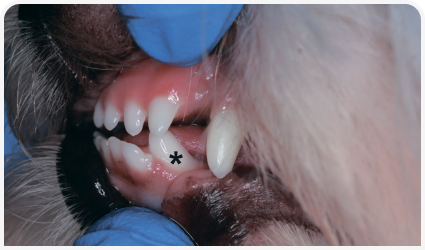

Сохраняющиеся молочные зубы — это молочные зубы, не выпавшие у животного к тому времени, когда прорезался аналогичный постоянный зуб, пришедший ему на смену. Чаще всего сохраняющимися молочными зубами оказываются клыки и резцы у собак той-пород (Рис. 10) (5). Сохраняющиеся молочные зубы приводят к скученности и изменению контура десен, что является фактором риска развития пародонтита. Помимо этого, они могут менять путь прорезывания, приводя к нарушению прикуса. Однако если постоянного зуба еще нет на месте сохраняющегося молочного, и при этом пародонт и сам молочный зуб здоровы, показания для его удаления отсутствуют.

Рисунок 10. Ши-тцу в возрасте 1 года под общей анестезией и в дорсальном лежачем положении для осмотра и лечения. Фотография демонстрирует ростральную часть верхней челюсти с сохраняющимися молочными резцами (левые с первого по третий и правые первый и второй [маленькие стрелки]) и сохраняющимися молочными правым и левым клыком верхней челюсти (крупные стрелки). Сохраняющиеся молочные зубы были удалены.